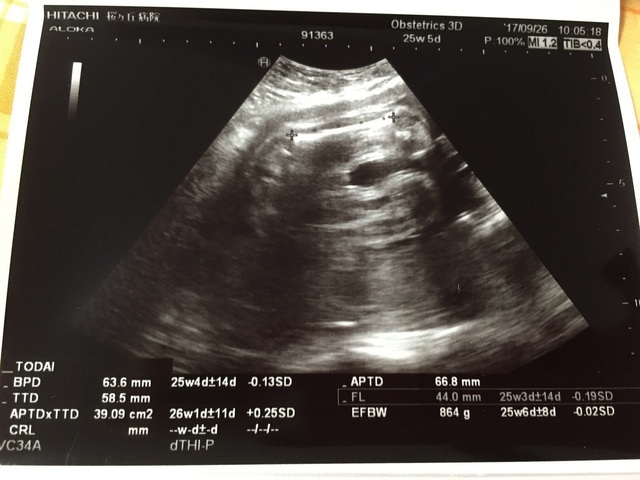

25週0日(25w0d・男の子)|のんかな さん(29歳)

エコー写真撮影時のエピソード:

初期からつわりが酷く、安定期に入ってもなかなか体調が良くならず大変でした。

一時的に良くなったのがこの週のときでした。

お腹自体はあまり大きくはならなかったんですが、赤ちゃんは、身長も体重も全てが標準で順調でした!

食事面では鉄分がなかなか取れず貧血気味だったので、処方された薬を飲んだり、葉酸サプリを買って飲んだりしていました。